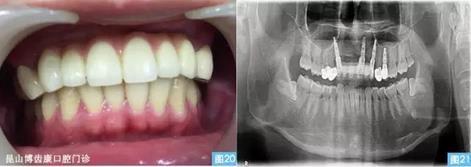

圖20圖21:(圖20左)完成最終修復(fù)后的口內(nèi)照,(圖21右)種植術(shù)后12個(gè)月曲面體層攝影。